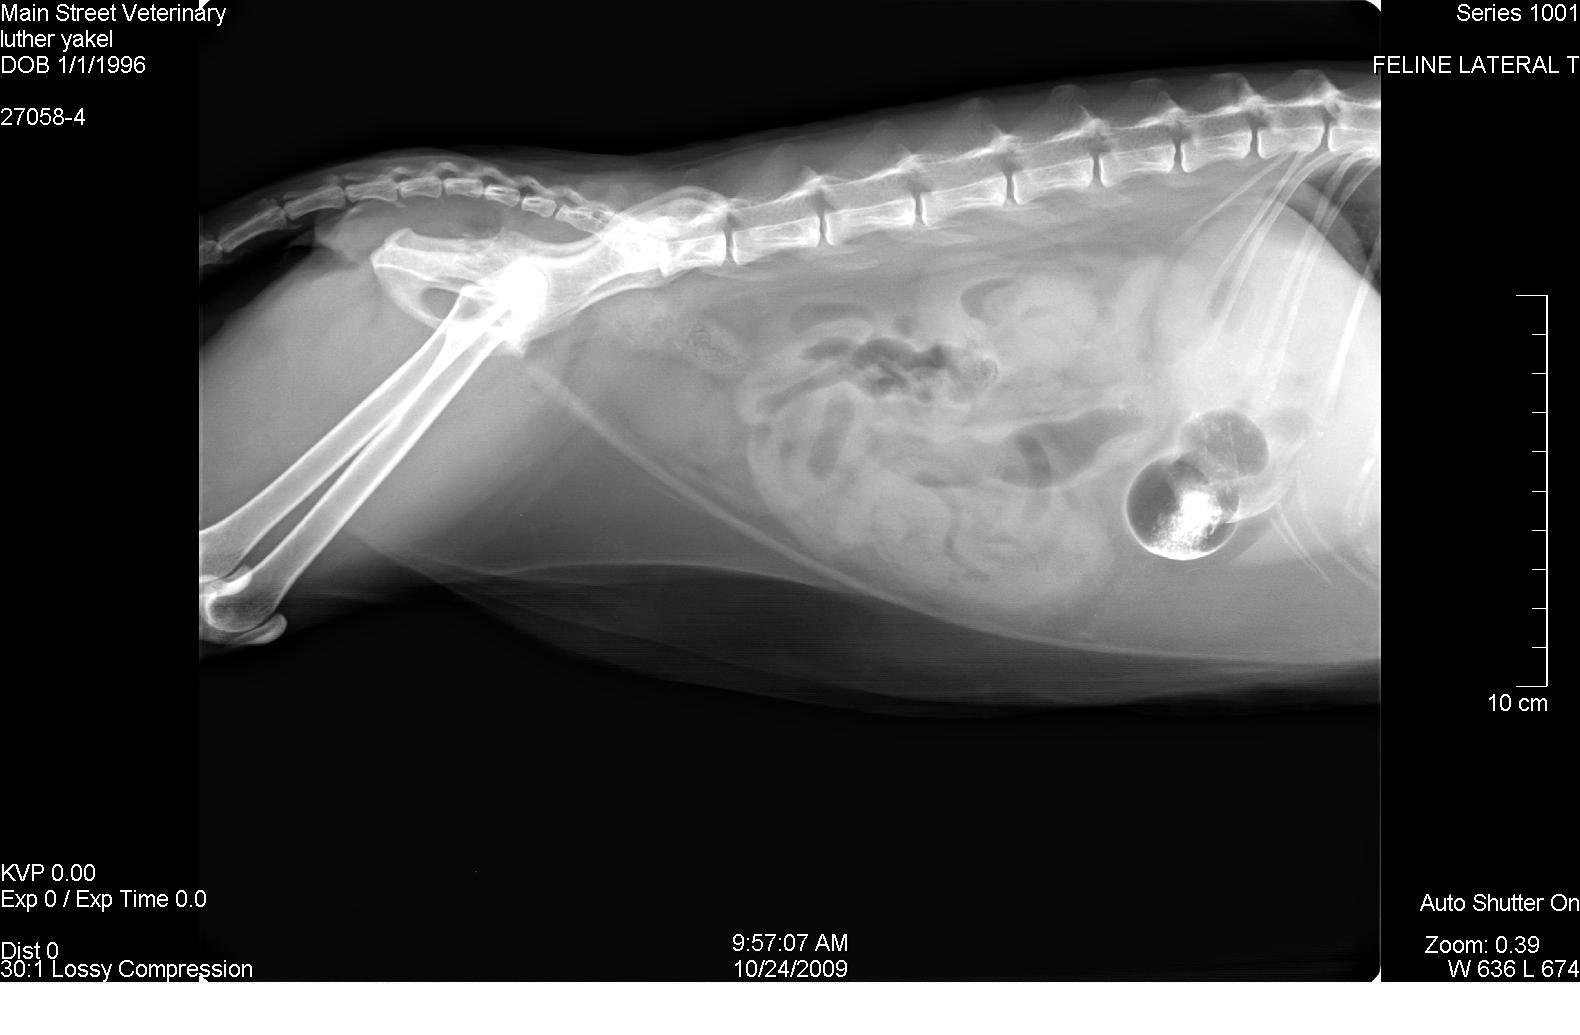

A 14-year-old MN DLH cat presented for anorexia, lethargy, and “not doing right”. The physical exam revealed depression, dehydration, and hypothermia. CBC revealed an elevated WBC count of 24,000 with a left shift and lymphocytopenia. Blood chemistry analysis was normal. Urinalysis revealed isosthenuria with neutral pH and negative culture. Radiographic Interpretation: (Images 1-3) The initial study shows a positive contrast distended stomach with evidence of segmental small bowel fluid and gas distention and adequate abdominal visceral serosal detail.

A 14-year-old MN DLH cat presented for anorexia, lethargy, and “not doing right”. The physical exam revealed depression, dehydration, and hypothermia. CBC revealed an elevated WBC count of 24,000 with a left shift and lymphocytopenia. Blood chemistry analysis was normal. Urinalysis revealed isosthenuria with neutral pH and negative culture. Radiographic Interpretation: (Images 1-3) The initial study shows a positive contrast distended stomach with evidence of segmental small bowel fluid and gas distention and adequate abdominal visceral serosal detail. The follow-up study reveals persistent gas and fluid distention of the stomach with retention of a small amount of contrast material. The degree and extent of small bowel fluid and gas distention has increased. The final study reveals generalized fluid and gas distention of the small intestine supportive of significant paralytic ileus or possibly mechanical ileus associated with a transient partially or intermittent foreign body within the distal small intestines.